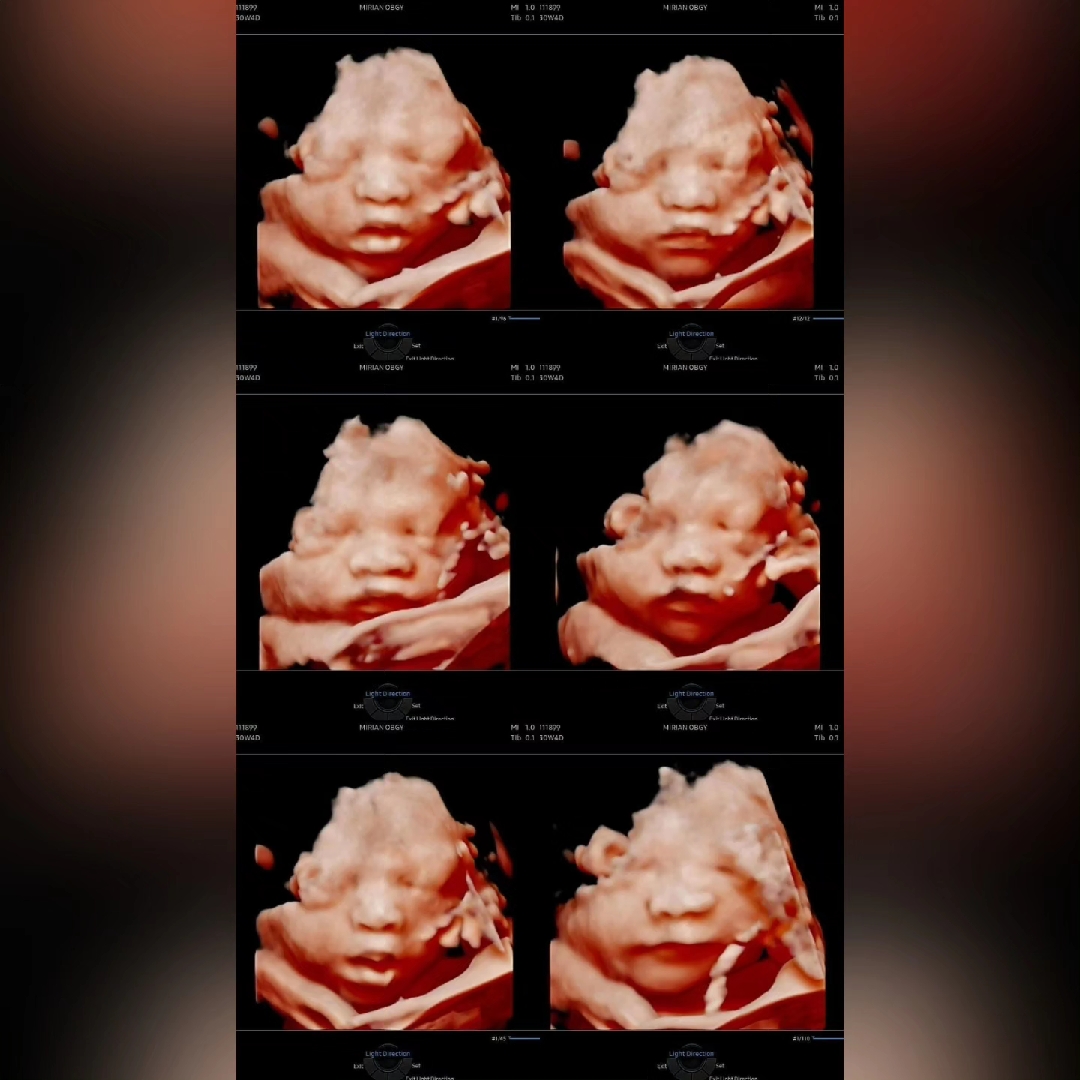

30주+4일 입체촘파❤️

28-30주에 입체초음파 많이 찍으시는거 같더라구요! (볼살 통통하게 올라 이쁠때라구요ㅎㅎ) 제가 다니는 병원은 24주에 찍고 별말씀 없으시길래 오늘가서 여쭤보니깐 30주부터는 잘 안보일수도있어서 권해드리진 않는다고 하시더라구요ㅜㅜ 원장님 진료보고 입체초음파할지 정해서 얘기해달라길래 진료봣는데.. 태반에 얼굴이 가려져서 입체촘파할때 잘안보일수도있다고..😭 그래도 마지막 입체초음파일수도있는데.. 한번보자!!하고 봣는데 다행이 제가 왼쪽으로 돌아누우니깐 같이 자세 바꿔줘서 성공적으로 보고왔어요..❤️ 첫아가이고 아들인데 아빠판박이네요..ㅋㅋ🥰💗 안보고왔으면 후회할뻔햇어요🫶🫶🫶 백일해주사도 맞고왔는데 원래 이렇게 아픈주사인가요..🥺 팔에 알배긴거같은 아픔이네요..🥲

감사합니다❤️ㅎㅎ 저두 태반에 얼굴가리고있데서 크게 기대는 안하고봤는데 다행히 너무잘보여주더라구요..🥰ㅎㅎㅎ